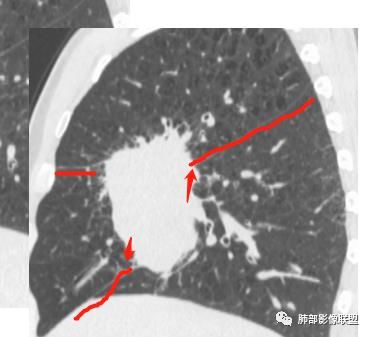

初学者:

可以看到斜裂一侧往上一侧往下,那么就是说病灶应该是起源中叶,往上,往下侵犯这样

只有这个位置起源得才能做到,将叶间裂上下往不同方向推

斜裂向下推移了,水平裂向上推移了。

下半段斜裂推移朝下

水平裂推移朝上

定在中叶应该没问题